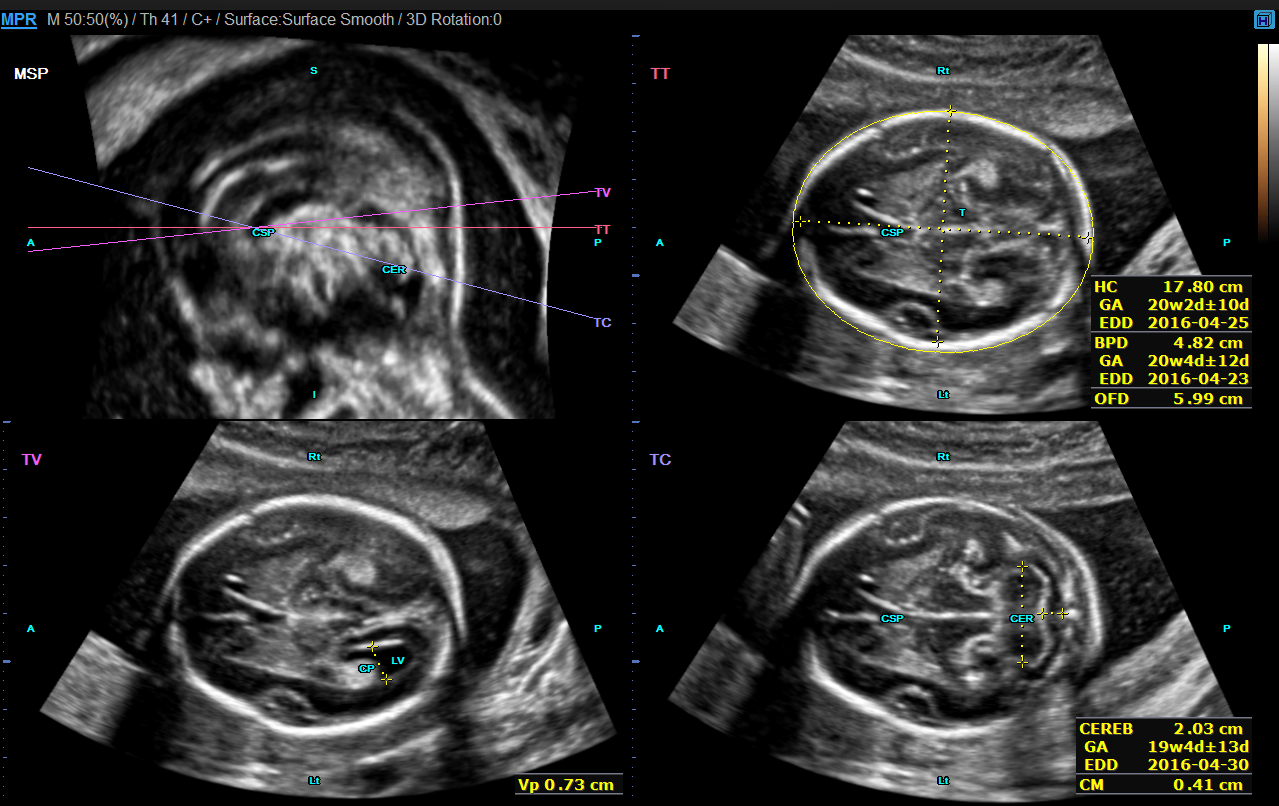

Le 5D CNS+™ est un module qui permet de générer et de reconstruire 9 plans de coupe automatiquement à partir d'une acquisition volumique sur le cerveau fœtal. Les calipers sont positionnés automatiquement par l'échographe à la demande de l'utilisateur.